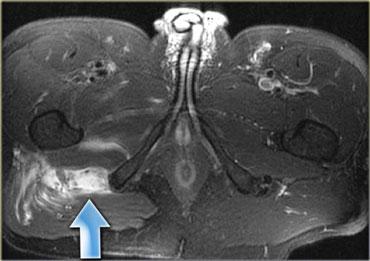

Bên trái cho thấy hình ảnh rách hoàn toàn cơ gân kheo trái tại chỗ nối cơ-gân.

Các gân bị bong tróc và có sự tích tụ dịch.

Bên trái là một bệnh nhân khác cũng bị đứt hoàn toàn gân cơ hamstring.

Có hình thái phù nề ngoại mạc cơ và kích thích thần kinh tọa.

Có thể xảy ra hội chứng hamstring.

Đây là tình trạng đau do sự hình thành sẹo sau chấn thương xung quanh thần kinh tọa (mũi tên).